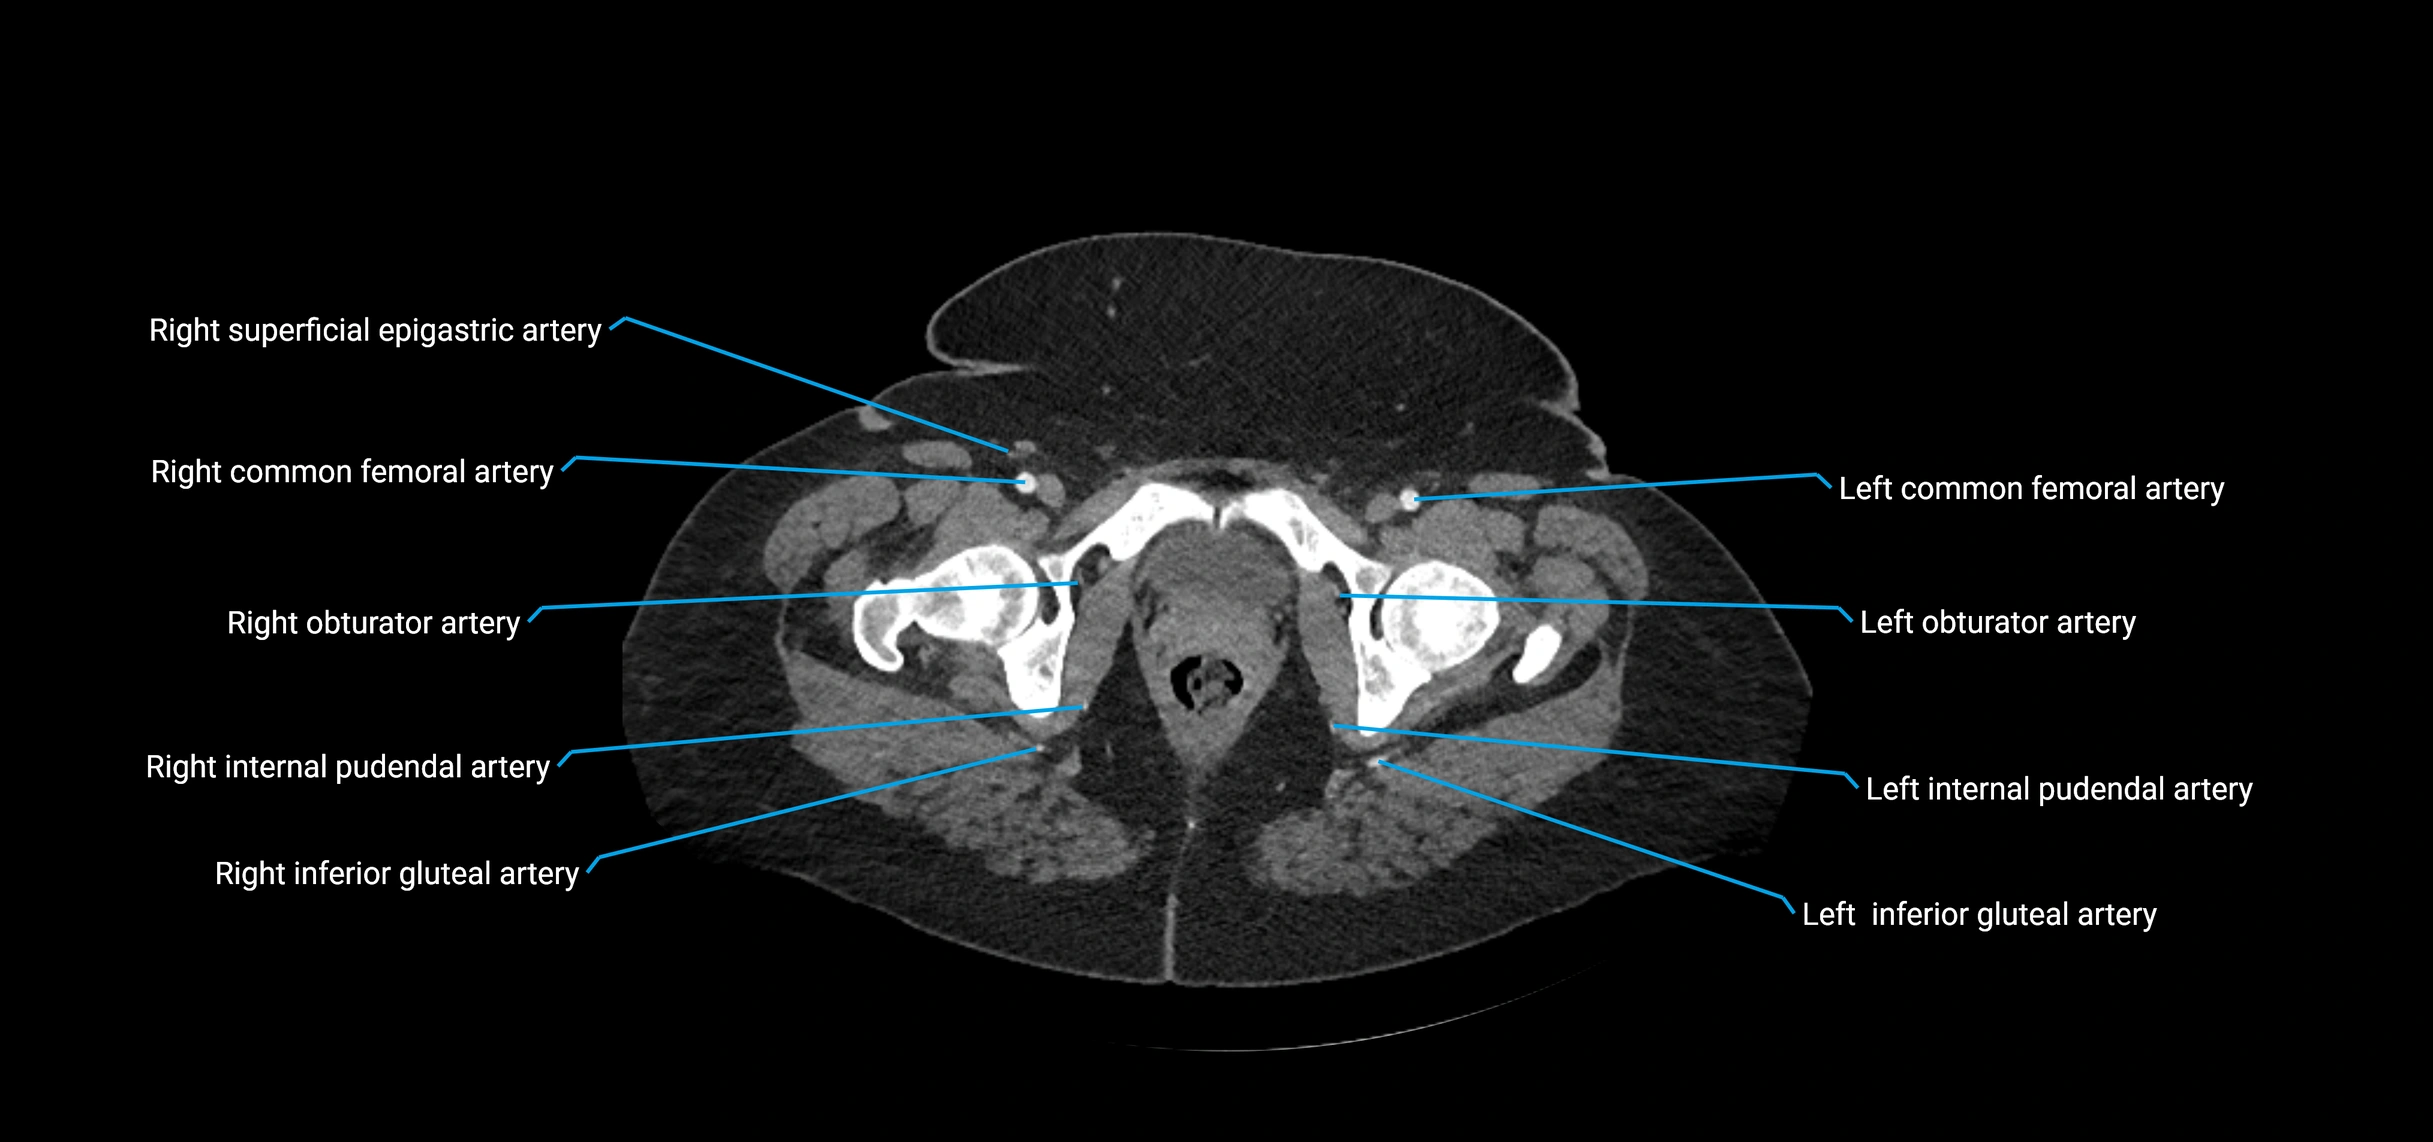

Contrast-enhanced CT (CTA):

• Gold standard for abdominal aortic imaging

• Provides excellent detail of lumen, wall, aneurysm, thrombus, and branch vessels

• Multiplanar and 3D reconstructions help in aneurysm measurement, stent graft planning, and dissection evaluation

• Detects acute rupture, traumatic injury, or occlusion with high sensitivity